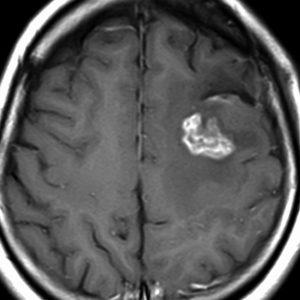

フレア画像です。左上前頭回の星細胞腫ですが,境界がとてもはっきりしていて限局性 localized single gyrus glioma です。びまん性 diffuseには見えません。IDH1の変異があり,1p/19qの欠失はないので星細胞腫グレード2です。上の例とは全く違う臨床像を示しますが,分子病理でも区別はつきません。頑張って早めに全摘出して治してしまった方がいいタイプです。再発を避けるために,supratotal resectionと言って,周囲の正常脳組織も10mmくらい余分に摘出します。